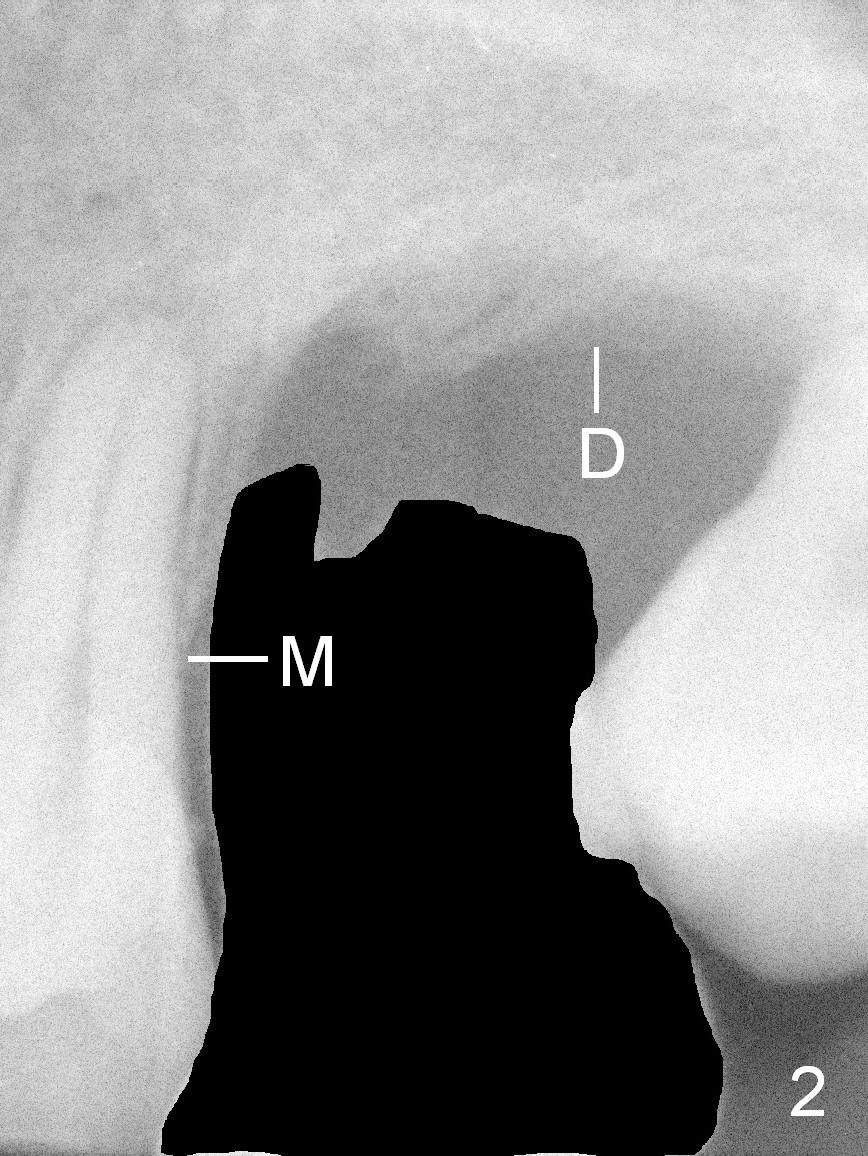

The smooth part of a tissue-level implant is equivalent to the cuff of cemented abutment associated with bone-level implant. The former is fixed, 3 mm, while the latter is variable, from 1-6 mm, offering flexibility in implant placement (in depth).

A 42-year-old man (XK) has perio-endo disease at the tooth #14. After root canal therapy (Fig.1), the tooth remains nonsalvageable. The bone loss is extensive (Fig.1 *) and uneven (more bone mesially than distally) after extraction (2% Xylocaine/1:50,000 Epinephrine). A bone-level implant is placed in an ideal depth (Fig.3 UF; Fig.4 SM), irrelevant of the gingival margin, first. Place bone graft distally (Fig.3 red circles) before choosing a proper abutment. For example, there is plenty of combination to choose cuff and abutment lengths for a SM or UF implant (Fig.4).